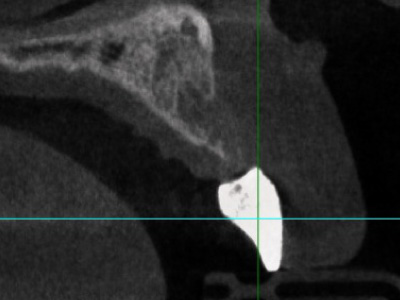

欧米人と比べてアジア人、特に日本人の上顎は下顎に比べて骨の量が少ない傾向にあります。さらに前歯は骨が薄く、女性は男性より薄いことが多いです。インプラントを支えるには、十分な骨の量が必要になってくるので、骨が少ないとインプラントがしっかりと生着しない事があります。

また、歯が無い期間が長いとだんだん骨が痩せていってしまうため、インプラント治療をする難易度が上がります。このように元々骨の量が少なく、インプラントを希望する患者さんの上の前歯の骨の量は少ない傾向にあるため、前歯のインプラントは難しいことが多いのです。

先述したように、非常に薄い骨の中にインプラントの埋入が求められることに加え、前歯のインプラント治療で審美的な仕上がりを実現するためには、インプラントの埋入位置が極めて重要です。わずか1 mmのズレや角度が5度違うだけで、最終的な見た目に大きな影響を与えるためです。ねじれた位置に埋入されと歪な被せ物しか作れなくなります。

また、特に下顎の前歯は神経が近いため、インプラント手術の際に神経が損傷するリスクがある点も難易度を高める要因の一つです。そのため、前歯のインプラント治療では、シミュレーションソフトを用いた精度の高い埋入計画が不可欠です。シミュレーションソフトにより、正確な位置にインプラントを埋入するための情報が得られます。

インプラントは骨の中に入るようにできるだけ細いものを使用していますが、それでも骨造成は必要です。